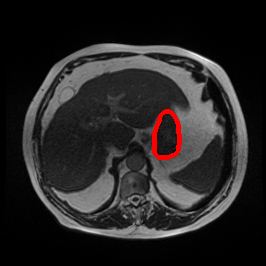

Ghosting Artifact

MRI GMAIMMbench Organ Recognition - Abdomen

Ghosting Artifact - L0 (Original)

L0

L0 (Original)

Ghosting Artifact - L1 (Moderate)

L1

L1 (Moderate)

Ghosting Artifact - L2 (Severe)

L2

L2 (Severe)

Question

Observe the MRI image. Can you identify the organ in the highlight area?

A fat B stomach C optic cup D gallbladder E optic disc

Ground Truth: B. stomach